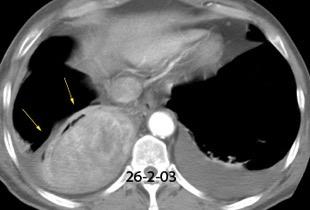

Diafragma “colgante” (“dangling sign”)

(“Dangling sign”)

TC. Mejor con multicorte. (reconstrucciones).

Asociación: Aire en pared.

Fracturas costal .Rotura esplénica. Neumoperitoneo.

Diafragma discontinúo Herniación de la grasa omental

Desser TS et al.The dangling diaphragm sign: sensitivity and comparison with existing CT signs of blunt traumatic diaphragmatic rupture. Emerg Radiol 2010